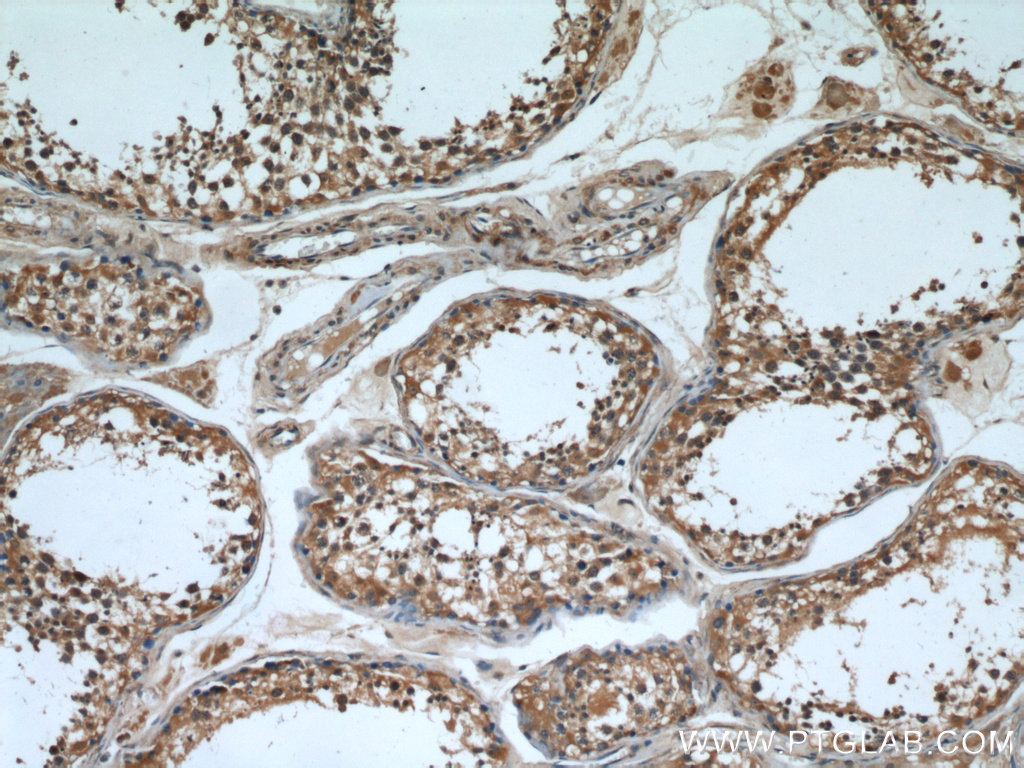

| Positive IHC detected in | human gliomas tissue, human testis tissue, human brain tissue Note: suggested antigen retrieval with TE buffer pH 9.0; (*) Alternatively, antigen retrieval may be performed with citrate buffer pH 6.0 |

| Immunohistochemistry (IHC) | IHC : 1:50-1:500 |